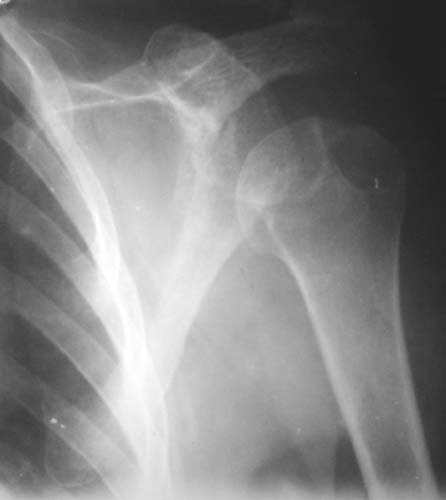

Уважаемые коллеги!Женщина, 60 лет. 3 недели назад упала с упором на отведенную левую руку. Почувствовала боль в левом плечевом суставе. За помощью не обращалась. 2 недели "мази и припарки". Затем - рентгенограмма (r1 и r2), жалобы на боли,ограничение движений...

Активное отведение 80 гр., при пальпации - головка плечевой кости безболезненно вправляется и тут же самостоятельно вывихивается. Наложена косыночная иммобилизация, рентгенография (r3) и МРТ.В нашем диагностическом центре МРТ исследование плечевого сустава выполнено впервые, опыта у нас маловато :(.Вопросы: уточнение диагноза? какие исследования провести? тактика лечения?

Как Вам известно, в некоторых случаях вывихи плеча сопровождаются разрывом ротаторной манжетки, отрывному перелому большого бугорка что приводит к потере наружной ротации и отведения плеча. На представленных рентгенограммах перелом не виден.

МРТ должен показать разрыв манжетки, но признаться я не большой эксперт по чтению МРТ сканов, хотя затемнение, отек мягких тканей по задней поверхности плеча видны Обычные рентгенограммы демонстрируют остеолизис в области большого бугорка.

1. На рентгене - нижний подвывих плеча и очаг остеолиза суставного бугорка с четкими контурами (вдавленный перелом на фоне остеопороза ? доброкачественная опухоль? аваскулярный некроз ? (хотя ни разу не слышал об аваскулярном некрозе плеча..)

Судя по снимкам, речь идTт о типичном случае Hill-Sachs Lesion. По этому поводу я позволю себе некоторый экскурс:

97 % всех вывихов плеча происходит по механизму комбинации отведения, разгибания и наружной ротации (А. Гринспан). В момент вывиха головка плеча ударяет о нижний край гленоида, что ведет к вдавленному или компрессионному перелому одной или обеих структур. Чаще всего, однако, повреждение возникает в задней латеральной области головки плечевой кости на переходе от головки к шейке. Этот диагноз можно выставить на основании рентгеновского снимка в переднезадней проекции с внутренней ротацией плеча. Несколько реже видно повреждение гленоида о передненижний перелом края. То, что мы называем Bankart Lesion. Это повреждение видно на ре. снимке в п.з. проекции при нейтральной позиции плеча. Разумеется хрящевые и мягкотканные повреждения (в смысле Банкарт) мы увидим лучше всего на ЯМР.